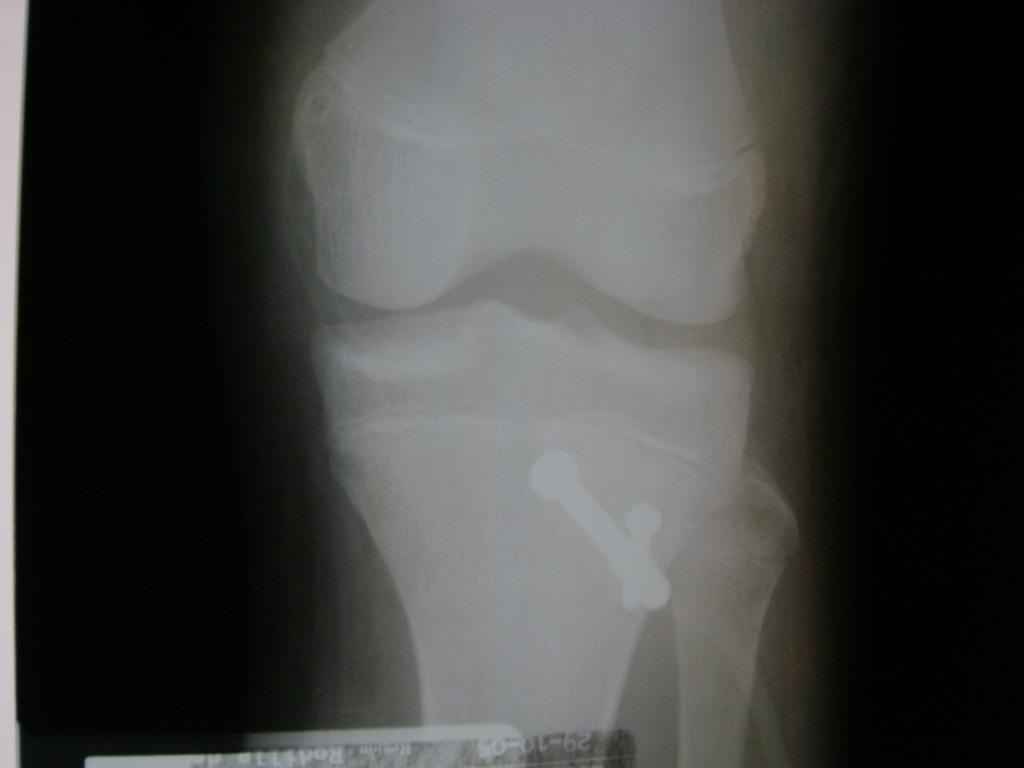

Fémur - Rodilla

La artroscopia de rodilla es un cirugía en el cual la estructura interna de la articulación es examinada ya sea para realizar un diagnostico o para realizar un tratamiento, este procedimiento se realiza utilizando un instrumento parecido a un pequeño tubo llamado artroscopio.